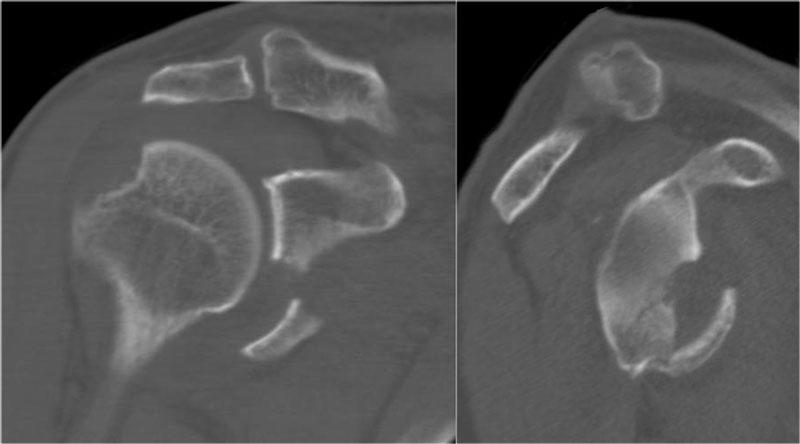

Trên tái tạo mặt phẳng chếch vành tai và mặt phẳng đứng dọc, mảnh gãy di lệch của bờ ổ chảo được thấy ở vị trí 3-6 giờ.

Trên hình ảnh mặt phẳng vành tai, quan sát thấy một khuyết xương Hill-Sachs lớn.

Đây là khuyết xương do hậu quả của sự va đập bờ ổ chảo vào chỏm xương cánh tay.

Tái tạo 3D của tổn thương Bankart xương lớn tại vị trí 2 – 6 giờ.